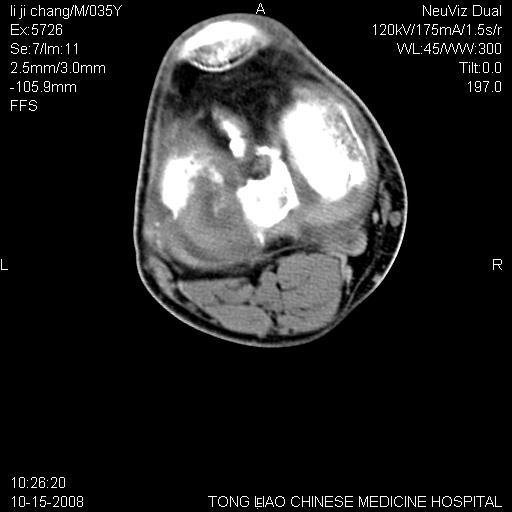

男,35岁,骨科诊断骨性关节炎。继往使用过激素,现股骨头坏死。膝关节病变,请会诊

一元论-----亦考虑为坏死

支持考虑无菌坏死

支持无菌坏死伴退行性骨关节病.

剥脱性骨软骨炎:是一种关节下软骨及软骨下骨缺血性坏死。

支持 无菌性坏死伴退行性骨关节病。